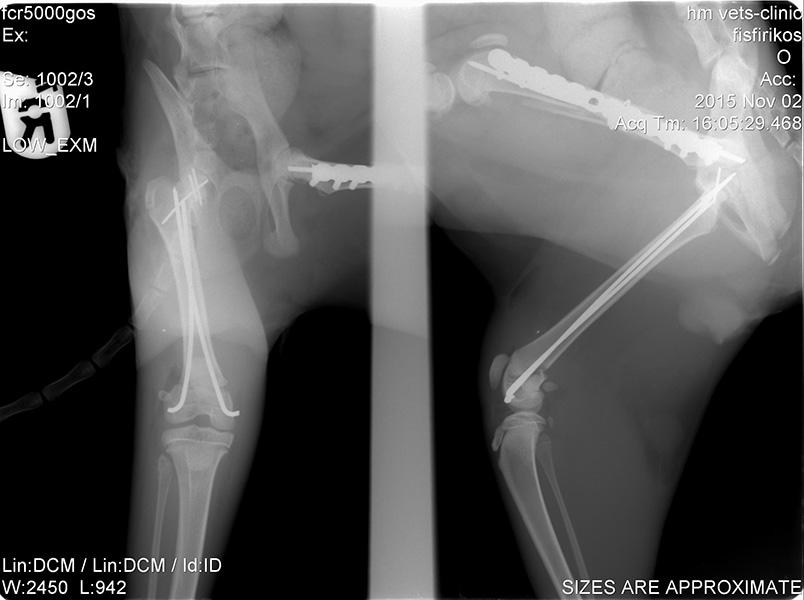

Ορθοπεδική

Ορθοπεδική

Το κτηνιατρείο hm vets αναλαμβάνει ψηφιακή ακτινογραφία, έλεγχο δυσπλασίας ισχίου, ορθοπεδική-νευροχειρουργική, χειρουργική μαλακών μορίων, οφθαλμολογία, εσωτερική παθολογία και εργαστηριακές εξετάσεις (αίματος, βιοχημικές, ανοσολογικές, ορμονολογικες, μοριακές και ιστοπαθολογικές).

Το κτηνιατρείο hm vets αναλαμβάνει ψηφιακή ακτινογραφία, έλεγχο δυσπλασίας ισχίου, ορθοπεδική-νευροχειρουργική, χειρουργική μαλακών μορίων, οφθαλμολογία, εσωτερική παθολογία και εργαστηριακές εξετάσεις (αίματος, βιοχημικές, ανοσολογικές, ορμονολογικες, μοριακές και ιστοπαθολογικές).